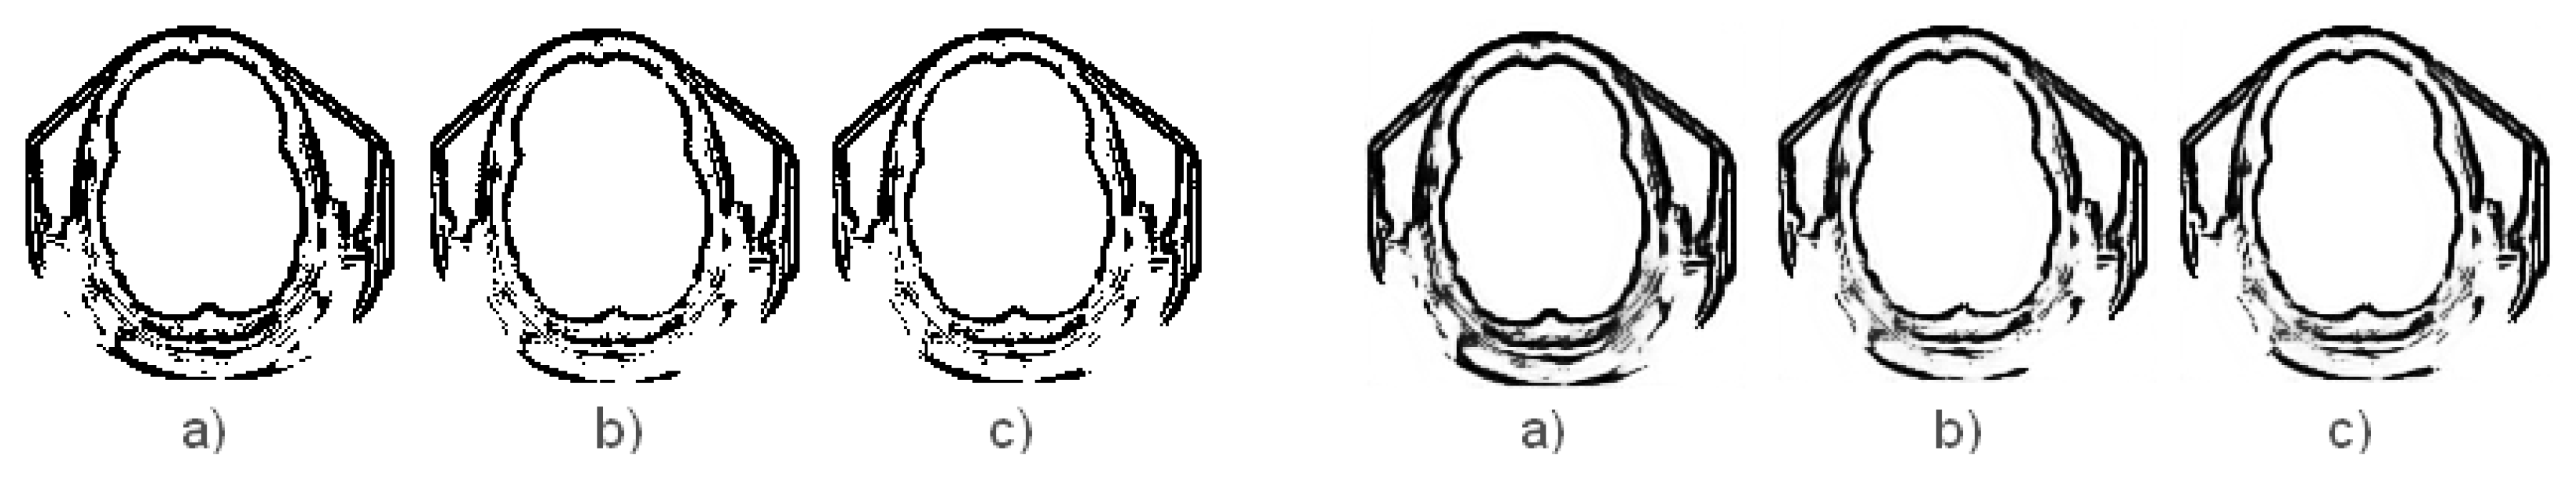

4.2. Representation of Results

- The operator has the results similar with the operator, so between and , operator performs better for image edge detection with ACO (Table 5).

- The best paper results is that the newly introduced operators and preserve better the edges of the medical image during the image denoising process with DnCNN (Table 5).